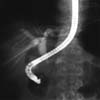

¿ªÇ༺ Ãé´ã°üÁ¶¿µ¼ú(ERCP)

³»½Ã°æ°ú

¹æ»ç¼± Åõ½Ã±â¸¦ ÀÌ¿ëÇÏ¿© Ãé´ãµµ Á¶¿µÀ»

ÅëÇØ ´ã¼®ÁõÀ̳ª ´ã³¶¿°ÀÇ º´º¯ºÎÀ§, °á¼®À̳ª

Á¾¾ç¿¡ ÀÇÇÑ ´ã°ü Æó¼â¸¦ ¾Ë¾Æº¸±â À§ÇÑ

°Ë»ç ¹æ¹ýÀ¸·Î Áø´Ü ¹× Ä¡·á ¸ñÀûÀ¸·Î

½ÃÇàµË´Ï´Ù. ÀϹÝÀûÀÎ ½Ã¼ú ¹æ¹ýÀº ´ÙÀ½°ú

°°½À´Ï´Ù.

´ãµµ¿Í

ÃéÀå ±â°ü(±×¸² 1)ÀÇ ÁúȯÀÌ ÀǽɵǴÂ

°æ¿ì¿¡ ³»½Ã°æÀ» ´ãµµÀÇ ³¡°ú ¸¸³ª´Â ½ÊÀÌÁöÀå

À¯µÎºÎ(±×¸² 2)±îÁö »ðÀÔÇÕ´Ï´Ù. Ä«¼¼ÅÍ(±×¸²

3)¸¦ À¯µÎ¸¦ ÅëÇØ ´ã°ü±îÁö »ðÀÔ ÈÄ Á¶¿µÁ¦¸¦

ÁÖÀÔÇÕ´Ï´Ù. ¹æ»ç¼± Åõ½Ã±â(±×¸² 4)¸¦

ÀÌ¿ëÇØ º´º¯ÀÇ À¯¹«¿Í Á¾·ù¸¦ ¹àÇô³À´Ï´Ù.